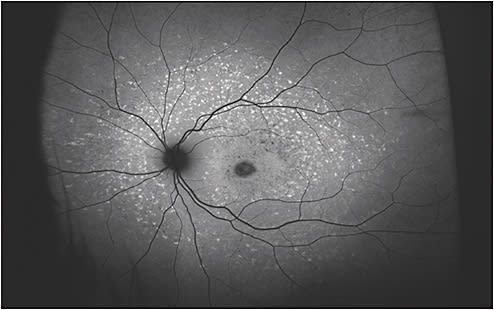

In Stargardt dystrophy, FAF imaging is particularly helpful in identifying highly autofluorescent lipofuscin-containing flecks, with a ring of peripapillary sparing of normal autofluorescence (AF) (Figure 3). Although this finding of peripapillary sparing is not pathognomic for ABCA4-mediated degeneration, it is highly suggestive of a hereditary etiology of disease.